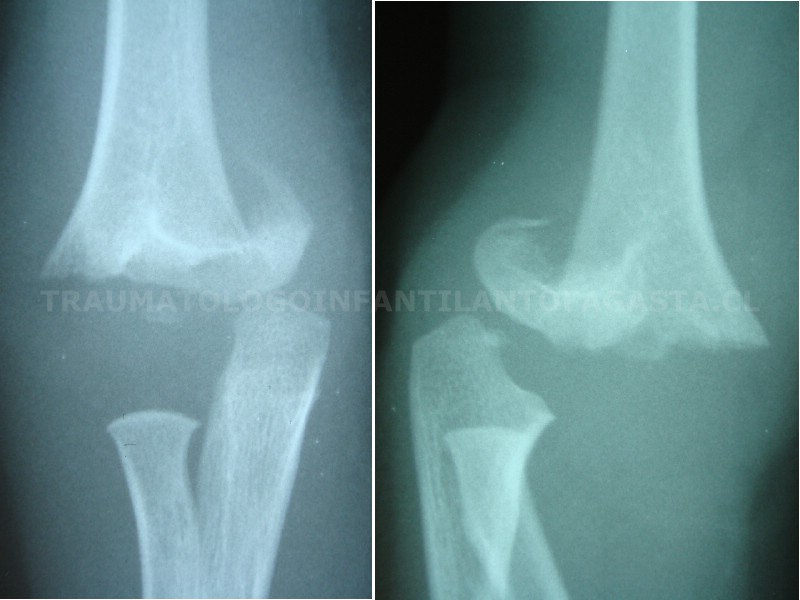

Fractura de codo

Fractura de codo inestable